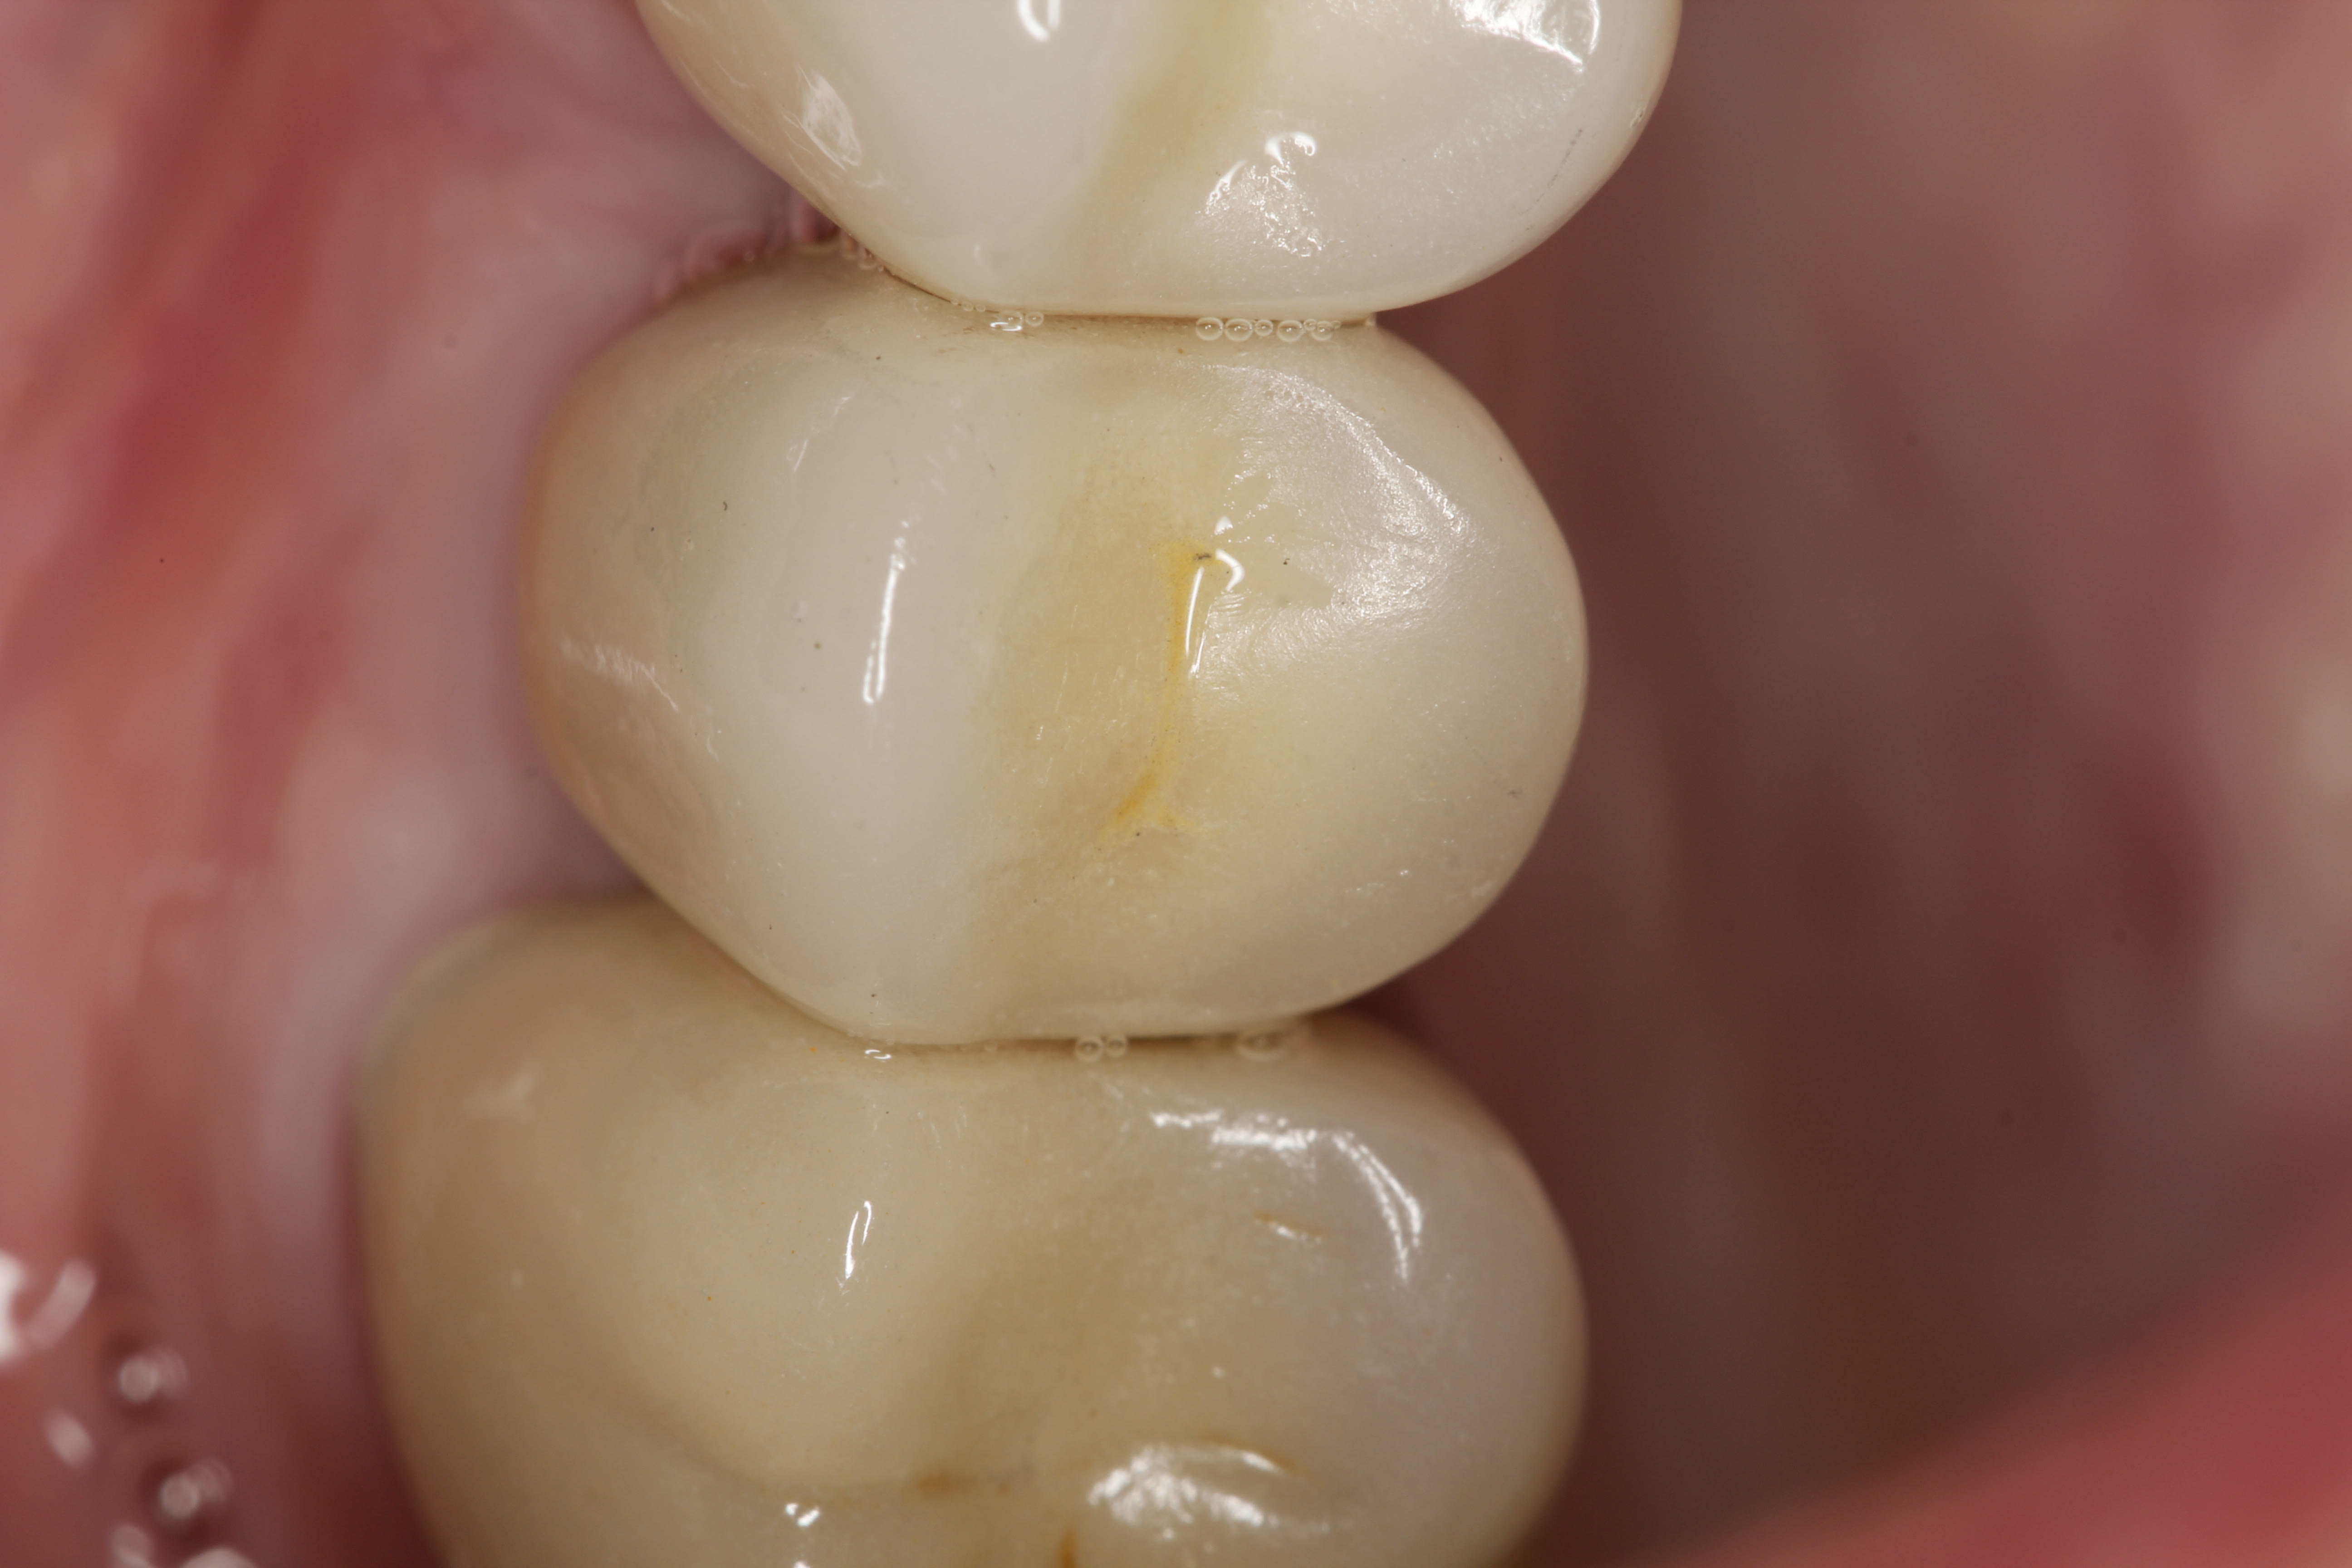

The final open-tray polyvinylsiloxane impression (Aquasil®, DENTSPLY International, Inc, www.dentsply.com) was also obtained at Visit 3. The impression coping was radiographically verified for accurate seating. The fixture analog was placed into the laboratory model, and a stock abutment (Genesis) was used by the laboratory to create a PFM crown with a screw-access hole in its occlusal surface (Figure 46).

In the prosthetic phase, the restorative dentist chose to use an indirect cementation technique to minimize the risk of cement entrapment/sepsis if the crown were to be cemented intraorally. In August 2012 the abutment and crown were tried in and, once proper seating and fit had been verified radiographically (Figure 47), the abutment was removed and the crown cemented extraorally with resin-modified glass-ionomer cement (FujiCem™, GC America, www.gcamerica.com). After removal of excess cement, the abutment–crown unit was then seated intraorally and torqued into the implant fixture to 35 Ncm using the standard platform-switched connection for this stock abutment. The access hole was sealed with Teflon tape and, after etching with 9.5% hydrofluoric acid, filled with nanohybrid composite resin (Renamel® NANO™, Cosmedent, www.cosmedent.com). The crown was then contoured, adjusted, and polished.

Figure 47 shows the stock abutment connected to the implant prior to extraoral cementation to the final PFM crown, which was followed by screw-retained placement (Visit 4). Figure 48 shows a good emergence profile, good gingival health, and a PD of 1 mm approximately 3 weeks after cementation (6-month follow-up), and Figure 49 confirms excellent esthetics and good occlusion at the 18-month follow-up visit (Visit 7).